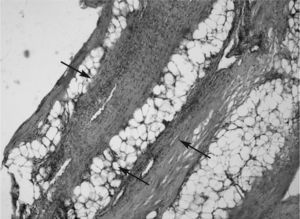

Paciente 2Varón de 50 años de edad, que presenta edema tórpido de 2 meses de evolución en ambas piernas que evoluciona progresivamente afectando a extremidades superiores y abdomen superior. En la exploración física se encontró una contractura en flexión de las 4 extremidades y lesiones circulares tipo morfea en tórax. Se inició tratamiento con prednisona (20mg/día), con discreta mejoría en las extremidades inferiores. La citología hemática mostró eosinofilia (23,9%; 1.910 eosinófilos totales), los estudios inmunológicos fueron negativos para ANA, ADNn y Scl-70. En la biopsia practicada con bisturí en técnica de huso no se observaron cambios patológicos en la piel, y el tejido profundo mostraba un proceso inflamatorio linfocítico intenso con engrosamiento de la fascia muscular e infiltración del tejido muscular y graso adyacente en forma difusa, no se evidenció presencia de eosinófilos (fig. 2). El estudio de posible extensión visceral fue negativo. Con base en estos datos se estableció el diagnóstico de FE y se inició tratamiento con prednisona a dosis de 50–70mg/día. A los 7 meses y ante la persistencia de la eosinofilia periférica, induración dérmica y clase funcional III, se decidió iniciar tratamiento con CsA a dosis de 5mg/kg/día. El paciente presentó una rápida respuesta clínica, y a las 4 semanas alcanzó una evidente reducción de la induración de la piel en las piernas, el abdomen y la cara anterior del tórax, las cifras de esosinófilos se corrigieron y el paciente incluso alcanzó una clase funcional I. Durante el segundo mes de tratamiento, el paciente presentó elevación de las cifras de presión arterial y discreta elevación de urea y creatinina, por lo que requirió reducción de la dosis de CsA a 3mg/kg/día, con lo que permaneció sin reactivación clínica. Debido a que el paciente es obeso y con hipertensión arterial, se decidió suspender el tratamiento de CsA a los 6 meses, que se sustituyó por metotrexato a 15mg/semanales y dosis bajas de deflazacort (3mg/día); hasta la fecha ha presentado dos episodios de reactivación.